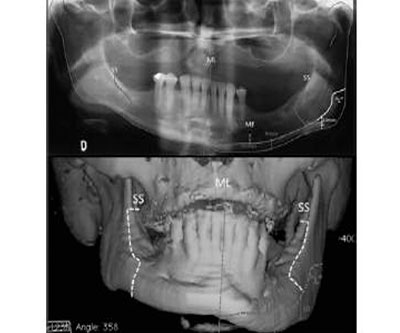

Injerto óseo con biomaterial granular en osteotomía maxilar segmentaria

Se describe el caso de una paciente de 24 años con mordida abierta anterior y discrepancias oclusales, tratada mediante osteotomía maxilar segmentaria y un injerto óseo utilizando gránulos de Bio-oss®.